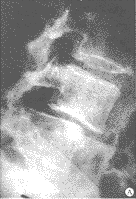

图1 1位45岁患者手术前、后X线照片

Fig 1 X-ray image of pre-operation and post-operation of a 45-years-old patient

A 45-year-old male with complaints of low lumbar pain and right low extremity pain; A: pre-operative X-ray shows degenerative spondylolisthesis of L4~5 (Ⅰ°); He was treated with interbody fusion by posterolateral insertion of

a single BAK. The post-anterior (B) and lateral (C) image

本组随访时间平均12.5个月(6~18个月),除1例影像学显示BAK融合器周围存在透明带, 判定为融合失败外,余皆达到临床融合(图1,2)。患者主观自我评定,12例满意,6例基本满意,2例认为可以。